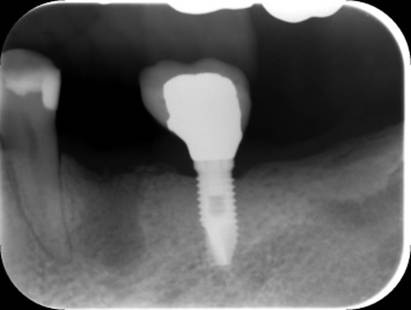

インプラントの隣の歯が破折し腫れていました

抜歯後6か月

抜歯部位にインプラントを追加しました。CBCT

上部構造もやり替えてジルコニア連結冠にしました